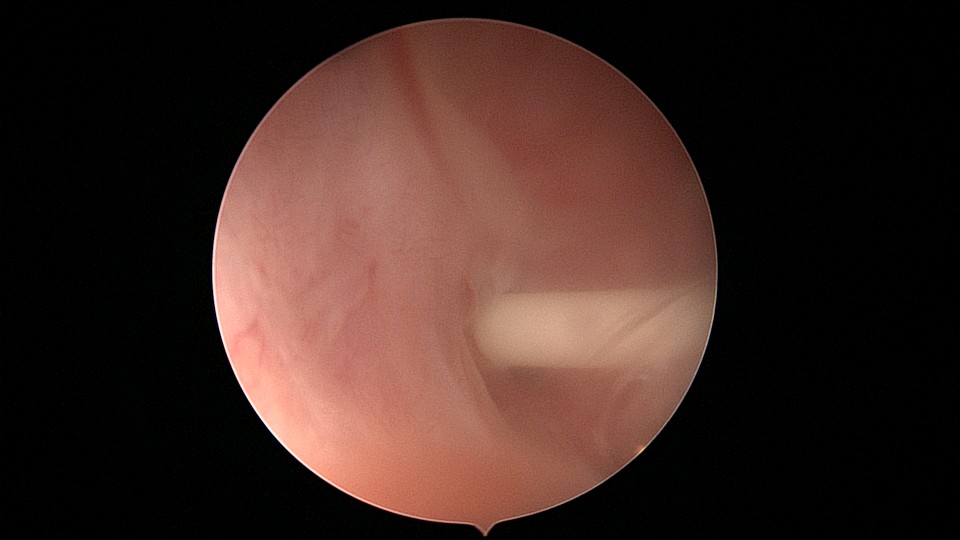

患者53岁,G3P1,剖宫产1次。安环13年,绝经8年,外院取环失败。患者阴道、宫颈及子宫萎缩,很难置入扩阴器,很难牵拉宫颈,宫颈外口位于前穹隆顶端,子宫极度前倾前屈位,且子宫与盆壁粘连,被拉长,宫腔镜很难进入,B超监护下异物钳扩张宫颈管上段及宫颈内口,宫腔镜艰难进入宫腔,见T型环两横臂嵌顿于两侧宫角,尾丝断裂,异物钳取出节育环,宫腔未见其他异常。